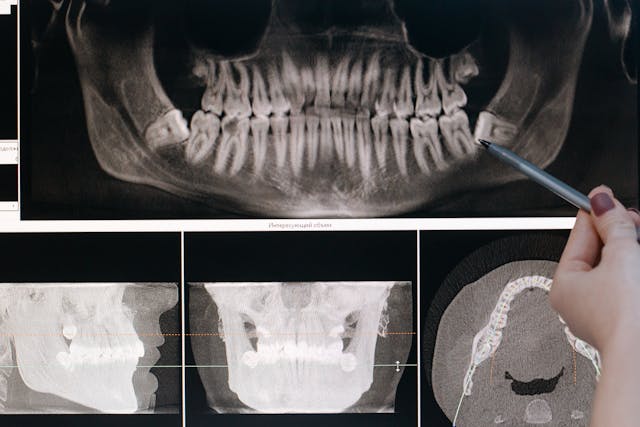

W kontekście zębów zatrzymanych szczególne znaczenie ma zdjęcie pantomograficzne, które pozwala ocenić obie szczęki jednocześnie.

W praktyce klinicznej już standardowe zdjęcie pantomograficzne pozwala z dużą dokładnością rozpoznać ząb zatrzymany oraz zaplanować dalsze postępowanie.

W większości przypadków wystarczające jest zdjęcie panoramiczne (pantomogram), które daje ogólny obraz uzębienia i struktur kostnych. Jest ono rutynowo wykonywane w diagnostyce ortodontycznej oraz przed zabiegami chirurgicznymi.

W bardziej skomplikowanych przypadkach, zwłaszcza gdy ząb zatrzymany znajduje się blisko ważnych struktur anatomicznych, lekarz może zalecić tomografię komputerową CBCT. Badanie to umożliwia:

- trójwymiarową ocenę położenia zęba,

- dokładne określenie relacji z nerwami i zatoką szczękową,

- precyzyjne zaplanowanie zabiegu chirurgicznego.

CBCT jest szczególnie przydatne przy zatrzymanych dolnych ósemkach oraz kłach górnych przemieszczonych podniebiennie.